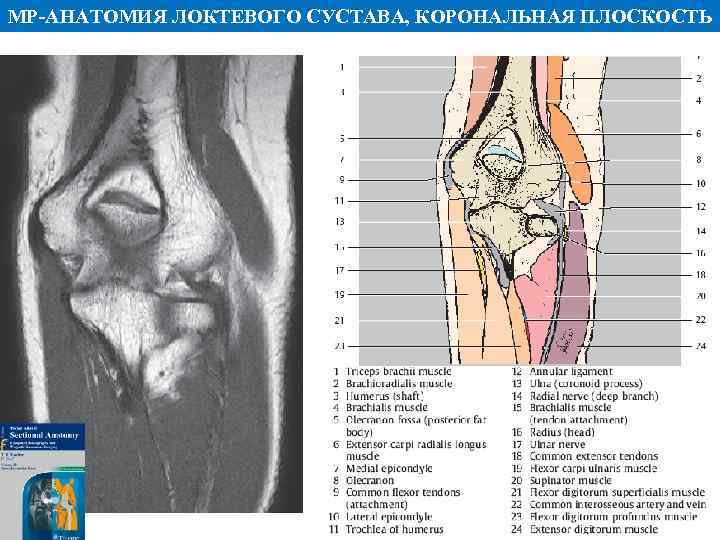

МР АНАТОМИЯ ЛОКТЕВОГО СУСТАВА, КОРОНАЛЬНАЯ ПЛОСКОСТЬ

МР АНАТОМИЯ ЛОКТЕВОГО СУСТАВА, КОРОНАЛЬНАЯ ПЛОСКОСТЬ